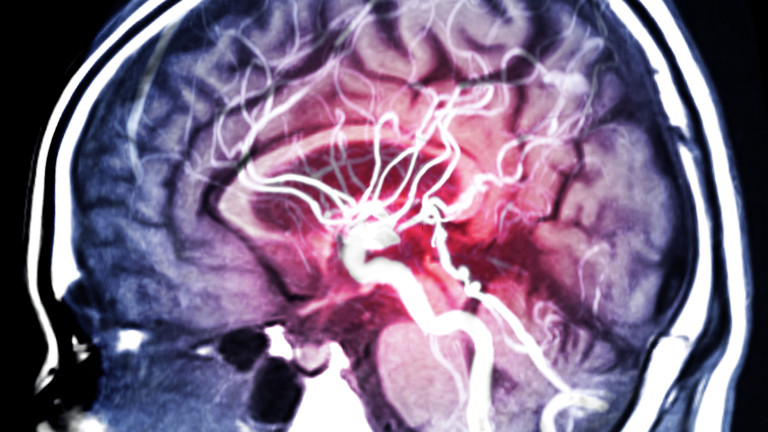

Учени от университета в Хюстън, САЩ, са успели да докажат, че оптимизмът е една от големите предпоставки за успешното възстановяване на хора с инсулт.

Източник: iStock

Те казват, че осакатяващите ефекти на мозъчния удар са по-малко при оптимистично настроените хора и при тях възстановяването протича много по-бързо, отколкото при хората с негативна нагласа.

Установено е, че в мозъка на оптимиста се наблюдават по-малко възпаления и вторични инсулти, което е важен аспект на възстановяването.